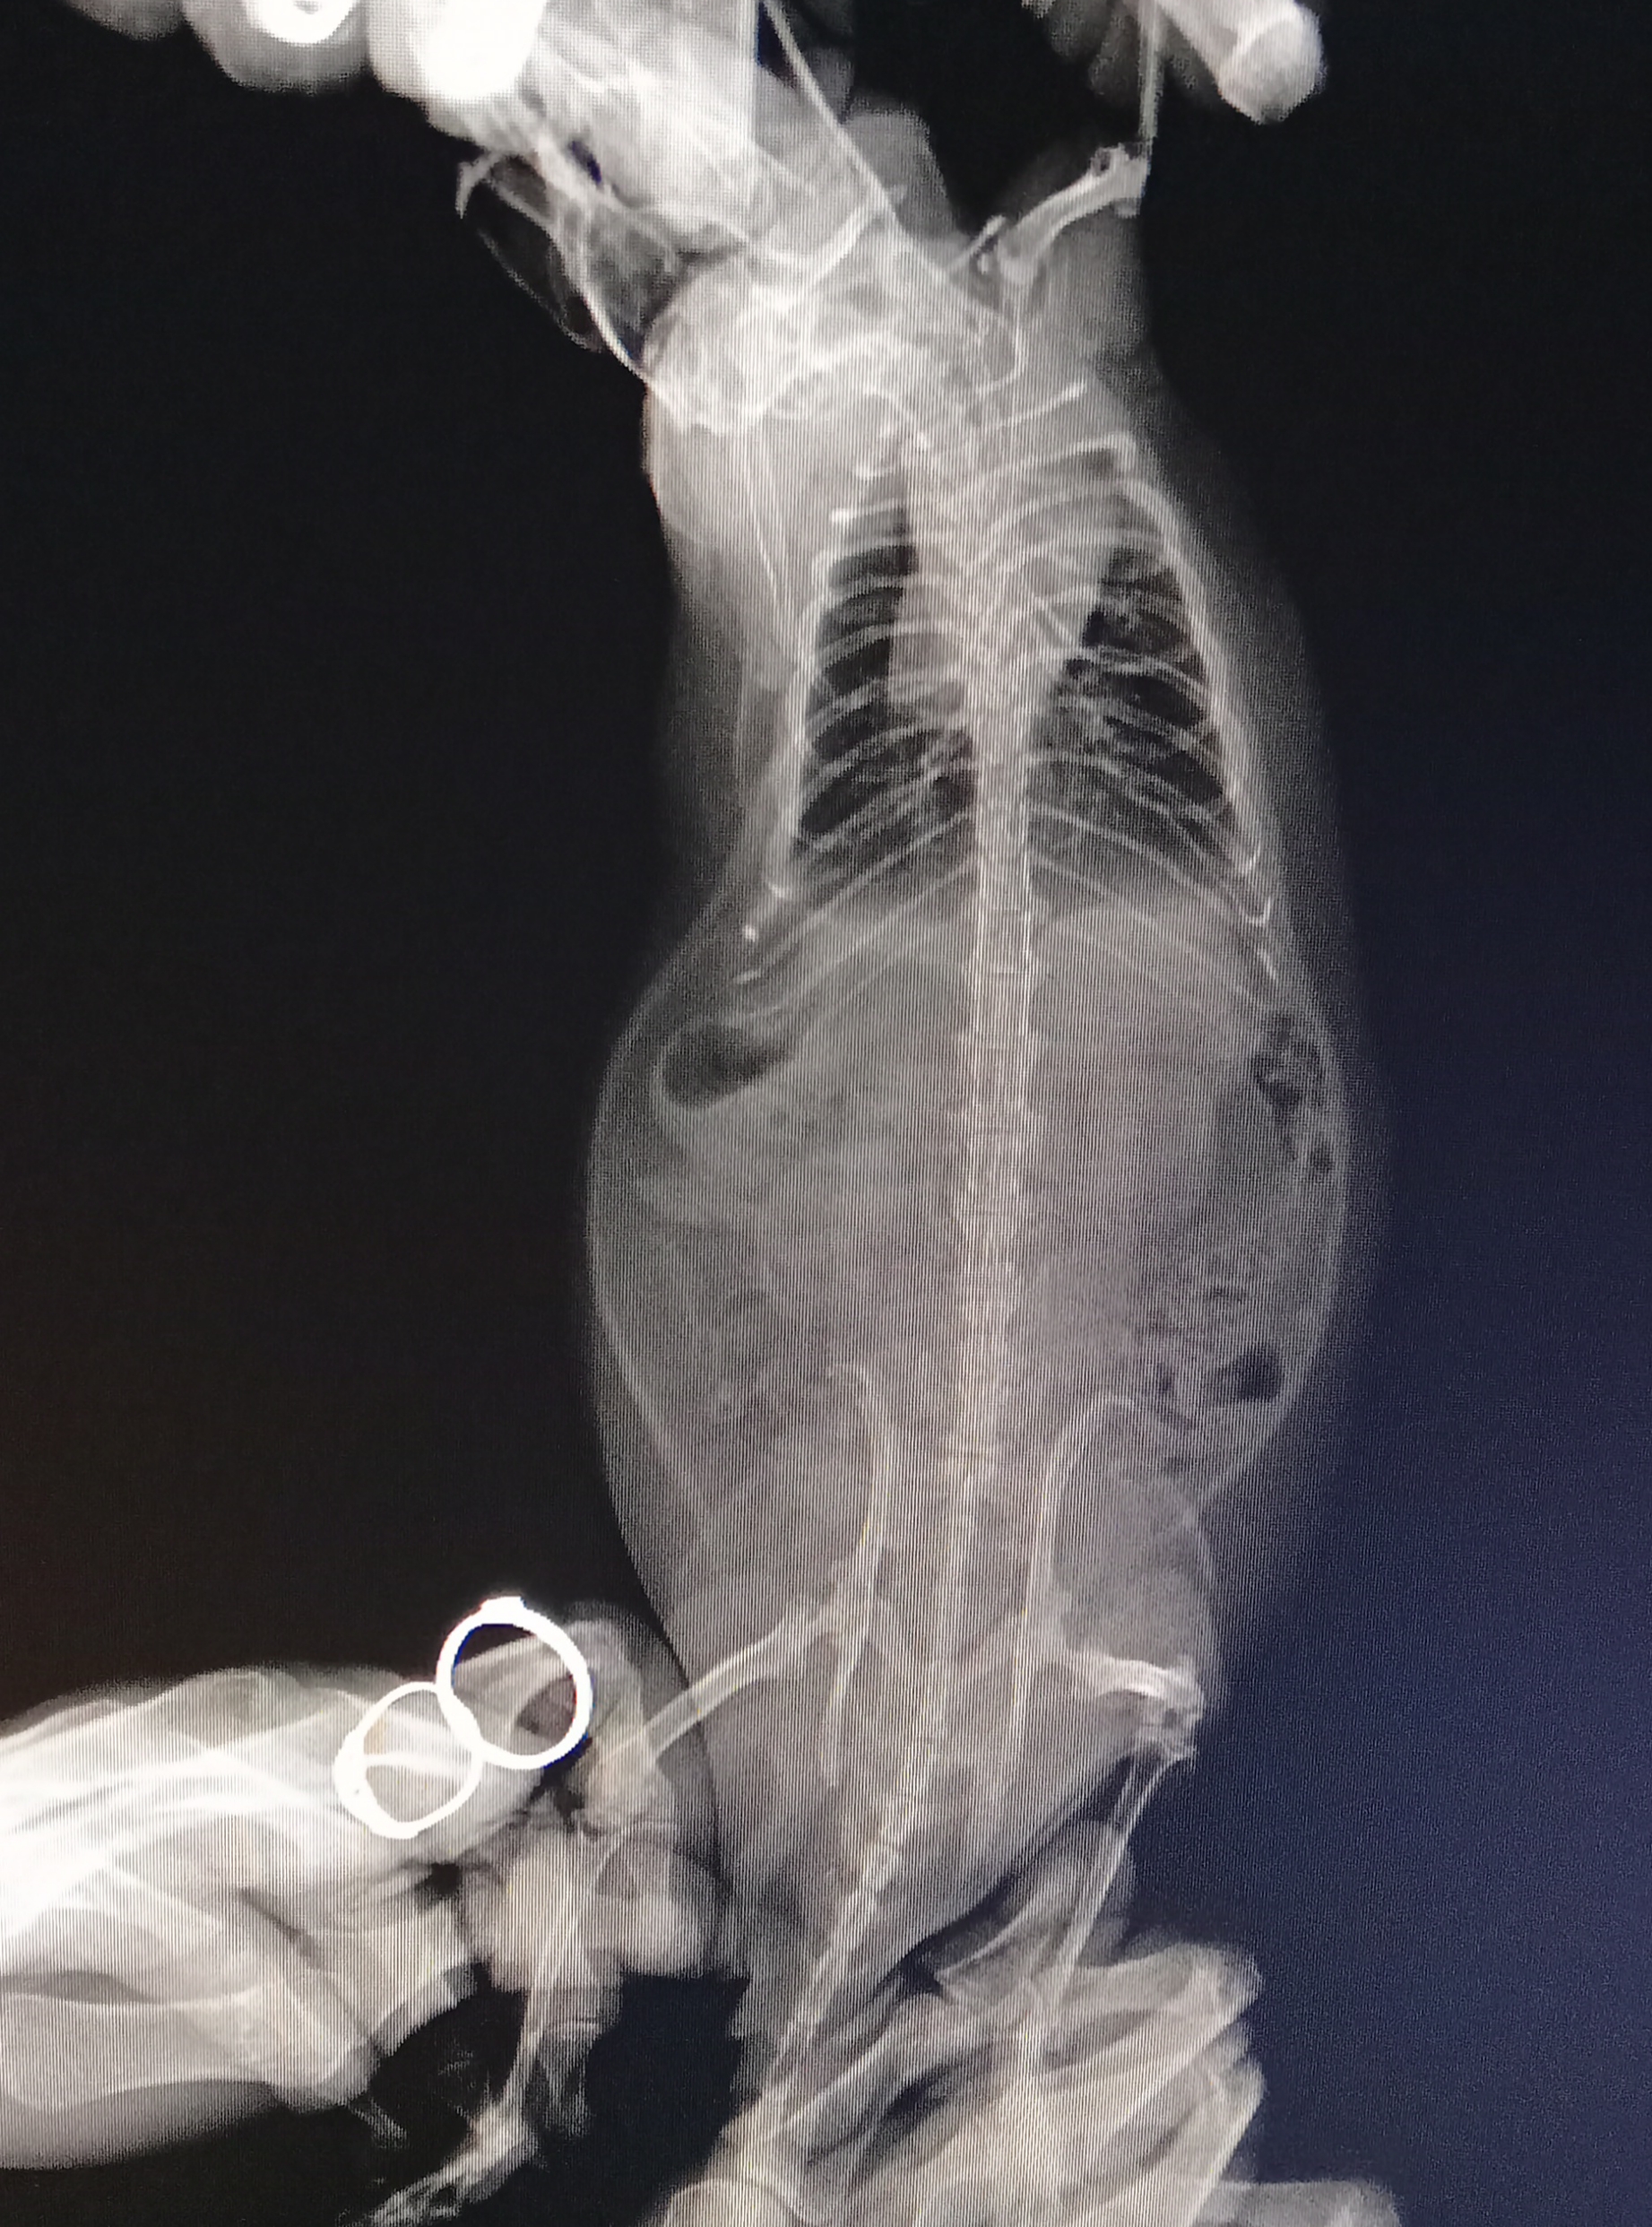

Здравствуйте. Очень нужна помощь. Крыса 1.7, заболел были сильные хрипы и сопли, дышал тяжело, шерсть взъерошена, нехватка кислорода (синели лапки и мордочка) . Были в клинике, что нам могли сделать, так это только рентген, так как специалиста по грызунам там нет. Назначили Амоксиклав и предположили, что возможно сердце (УЗИ не делают). Рекомендовали пропить ветмедин и мочегонку.

Антибиотик пропили только две недели, чихать -хрипеть перестал, но состояние не улучшается, только хуже становится. Похудел, можно сказать перестал есть, хотя до этого аппетит был как у трёх крыс вместе, апатичный, постоянно лежит голову свесив. Дыхание частое поверхностное. Из одного глаза то ли порфирин, то ли кровь.